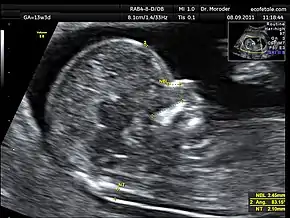

A nuchal scan or nuchal translucency (NT) scan/procedure is a sonographic prenatal screening scan (ultrasound) to detect chromosomal abnormalities in a fetus, though altered extracellular matrix composition and limited lymphatic drainage can also be detected.[1]

There are two distinct measurements: the size of the nuchal translucency and the thickness of the nuchal fold. Nuchal translucency size is typically assessed at the end of the first trimester, between 11 weeks 3 days and 13 weeks 6 days of pregnancy.[3] Nuchal fold thickness is measured towards the end of the second trimester. As nuchal translucency size increases, the chances of a chromosomal abnormality and mortality increase; 65% of the largest translucencies (>6.5mm) are due to chromosomal abnormality, while fatality is 19% at this size.[2] A nuchal scan may also help confirm both the accuracy of the pregnancy dates and the fetal viability.

Procedure

Nuchal scan (NT procedure) is performed between 11 and 14 weeks of gestation, because the accuracy is best in this period. The scan is obtained with the fetus in sagittal section and a neutral position of the fetal head (neither hyperflexed nor extended, either of which can influence the nuchal translucency thickness). The fetal image is enlarged to fill 75% of the screen, and the maximum thickness is measured, from leading edge to leading edge. It is important to distinguish the nuchal lucency from the underlying amniotic membrane.[8]

Normal thickness depends on the crown-rump length (CRL) of the fetus. Among those fetuses whose nuchal translucency exceeds the normal values, there is a relatively high risk of significant abnormality.

How to define a normal or abnormal nuchal translucency measurement can be difficult. The use of a single millimeter cutoff (such as 2.5 or 3.0 mm) is inappropriate because nuchal translucency measurements normally increases with gestational age (by approximately 15% to 20% per gestational week from 10 to 13 weeks).[9] At 12 weeks of gestational age, an "average" nuchal thickness of 2.18mm has been observed; however, up to 13% of chromosomally normal fetuses present with a nuchal translucency of greater than 2.5mm. Thus for even greater accuracy of predicting risks, the outcome of the nuchal scan may be combined with the results of simultaneous maternal blood tests. In pregnancies affected by Down syndrome there is a tendency for the levels of human chorionic gonadotropin (hCG) to be increased and pregnancy-associated plasma protein A (PAPP-A) to be decreased.